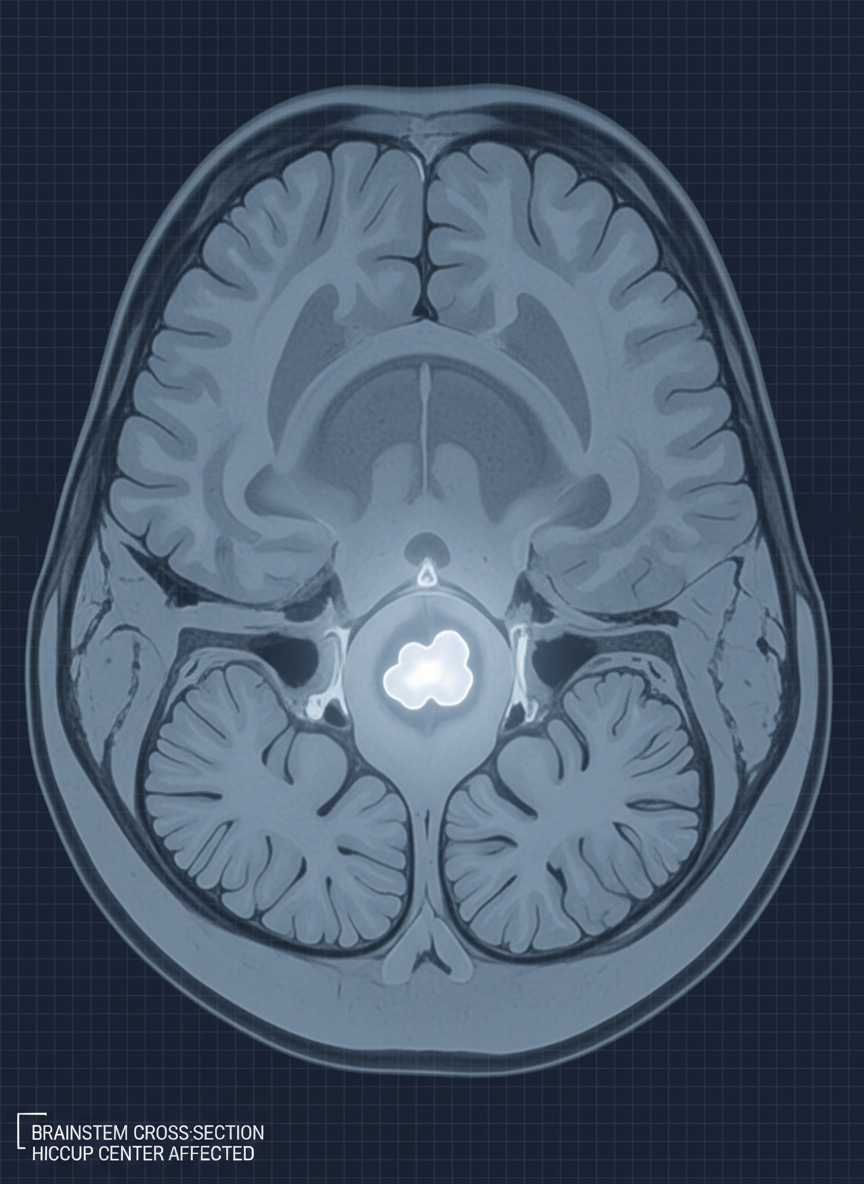

2. 뇌 질환

가장 심각하게 봐야 할 경우 중 하나인데요, 뇌간(brainstem) 부위의 뇌졸중, 뇌종양 같은 질환이 딸꾹질 중추를 자극해 발생하기도 합니다. 특히 어지럼증, 팔다리 마비, 시야 이상 등 신경학적 증상이 동반된다면 즉시 병원을 찾아야 합니다.